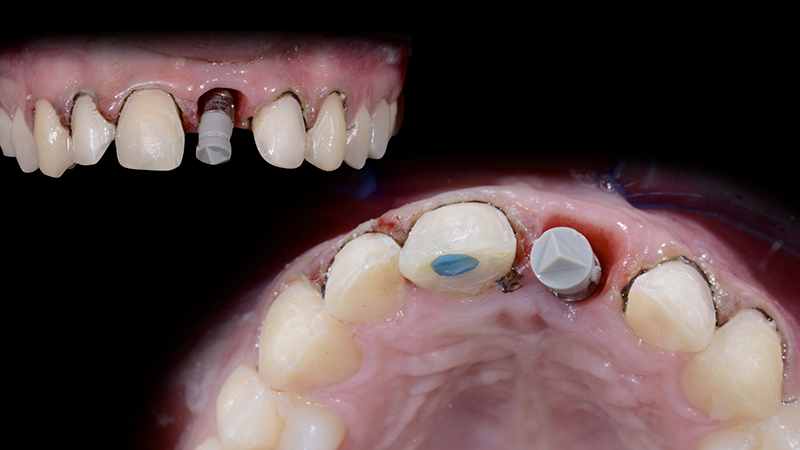

6. Impronte definitive per la realizzazione del provvisorio immediato. Una volta scansionato lo scan body, si disegna il profilo di emergenza (Base Line) sulla maschera gengivale. Successivamente, selezionando la porzione anatomica del dente 1.1 (Copy Line), il dente 2.1 verrà creato automaticamente e fresato in PMMA, grazie al software di progettazione. Il restauro del 2.1 è cementato alla T-base e avvitato all'impianto con una coppia di 20 Ncm. Il provvisorio, grazie al profilo di emergenza personalizzato, favorirà il condizionamento dei tessuti molli supportandoli e sigillando i margini del gap chirurgico. Ciò proteggerà la matrice collagenica sottostante, garantendo un risultato finale di successo (Fig. 16a, Fig. 16b, Fig. 16c, Fig. 16d).

Pianificazioner digitale del secondo dente provvisorio avvitato sull'impianto

Fig. 16a - Pianificazione digitale del secondo dente provvisorio avvitato sull'impianto.

Dente fresato in PMMA

Fig. 16b - Dente fresato in PMMA.

Secondo dente provvisorio avvitato

Fig. 16c - Secondo dente provvisorio avvitato.